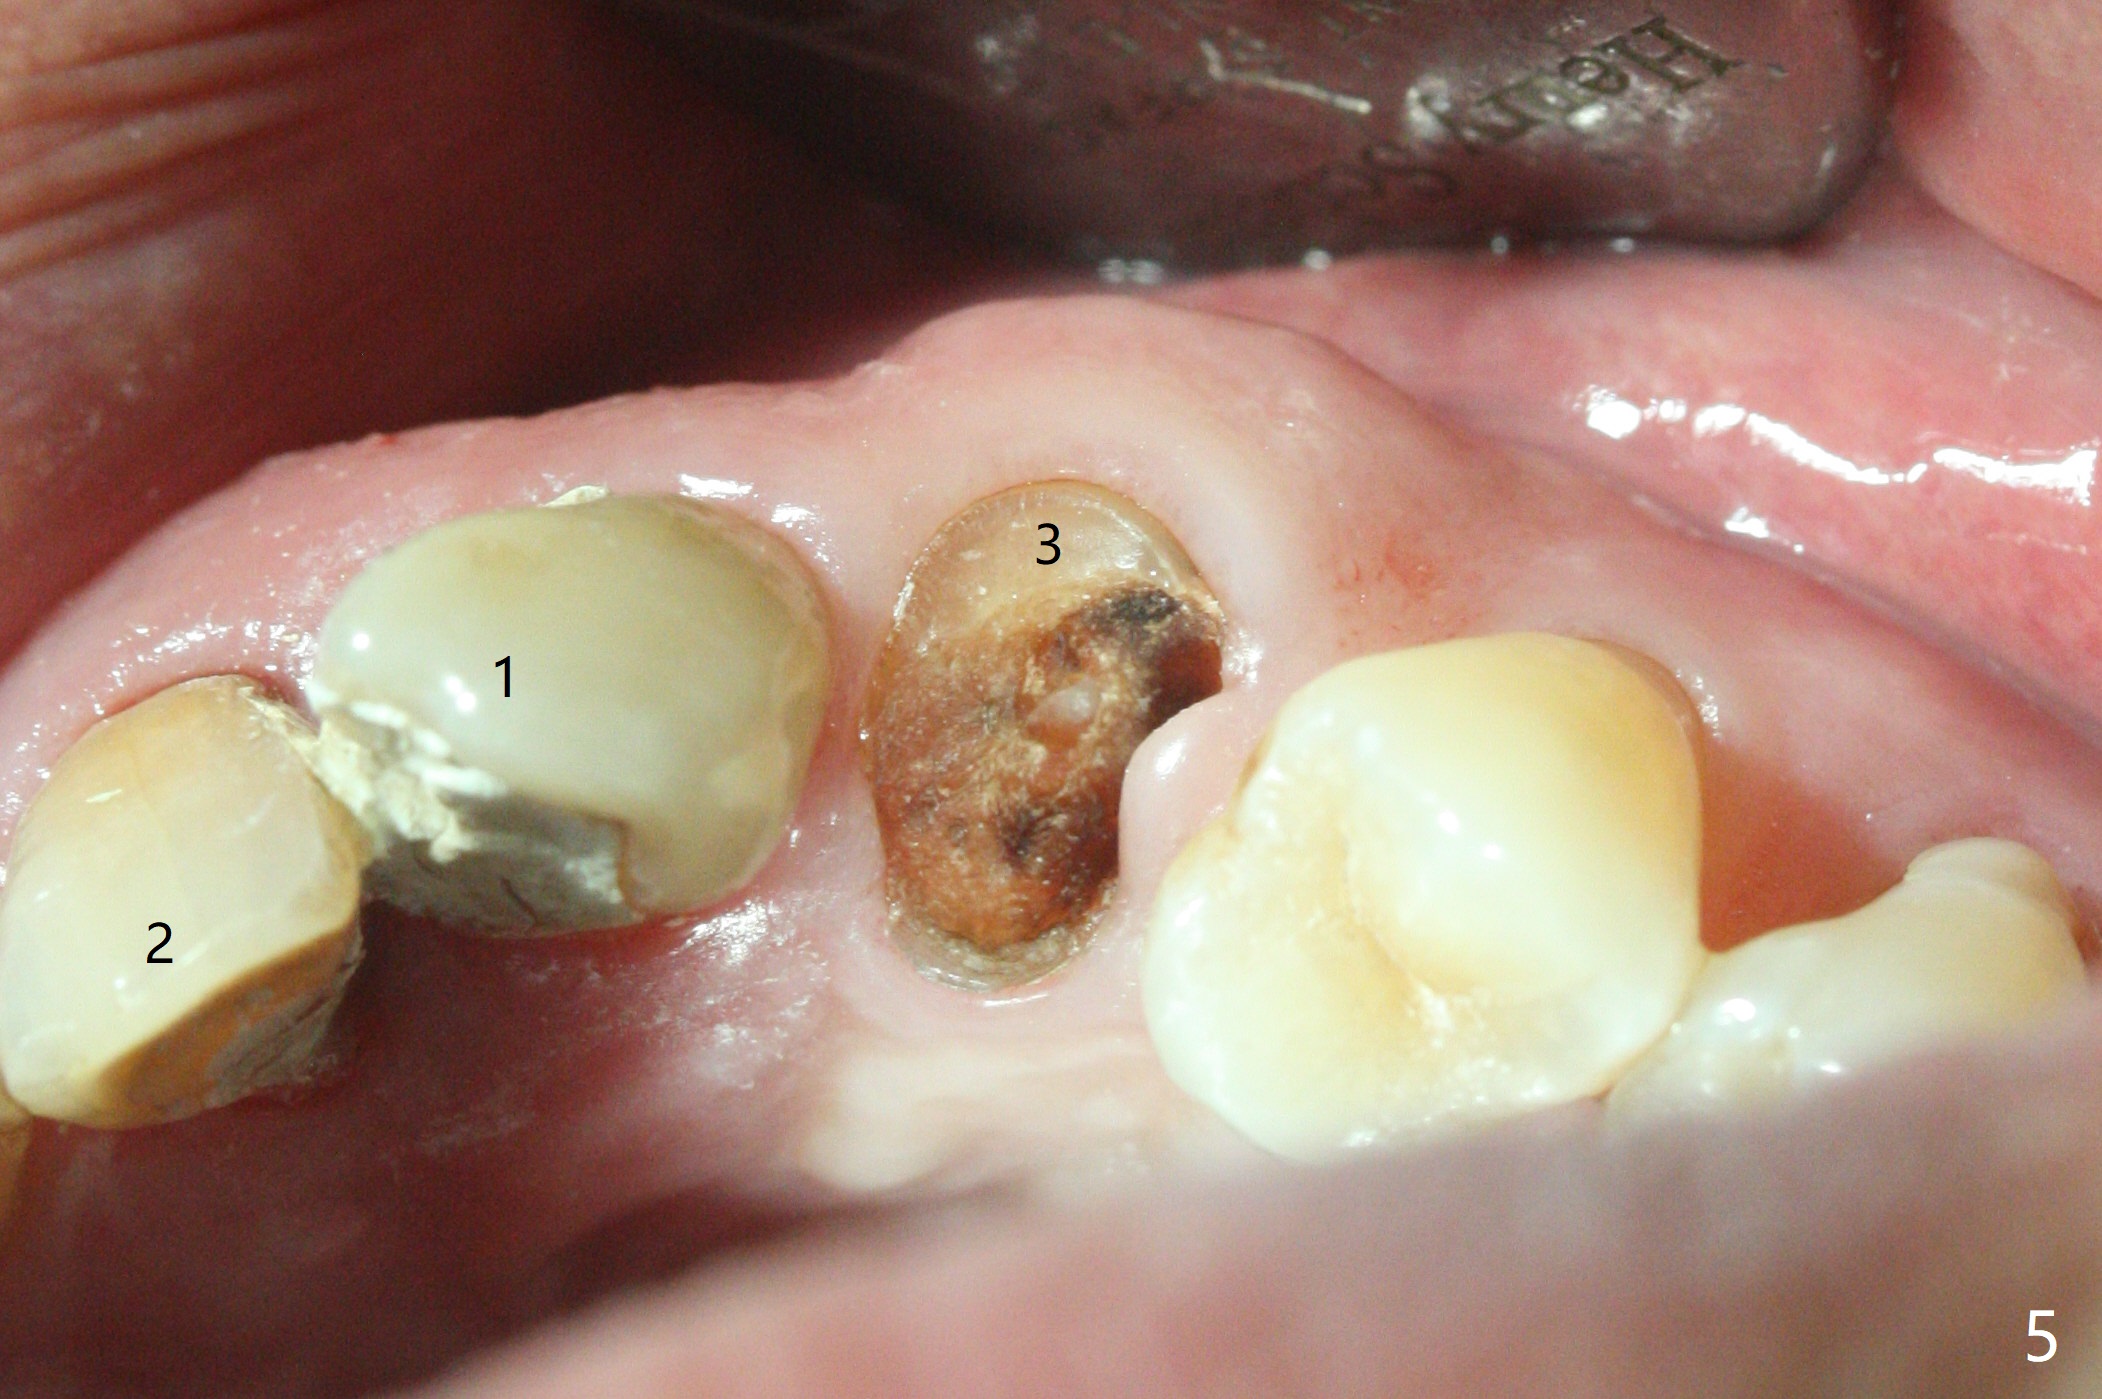

64岁男要求拔除左上3(图一,二),将使用Piezo P3 tip(图三)松动牙根,可行?其实图三是G6,used for removal of calculus from a wide plane. G:可能代表general use or general dentistry,而P牙周(图四)。P3(买了好久,不知道用处)特别细长,容易进入牙周膜,但愿在小功率的普通Piezo Scaler (超声洁牙机)作用下,P3能切断牙周膜,午饭后尝试。其实尖牙无症状(图五),中切牙(在侧切牙位置上)因近中深龋造成牙龈炎症,在病人要求下,清除龋坏后,填入临时充填物(图五,六)。